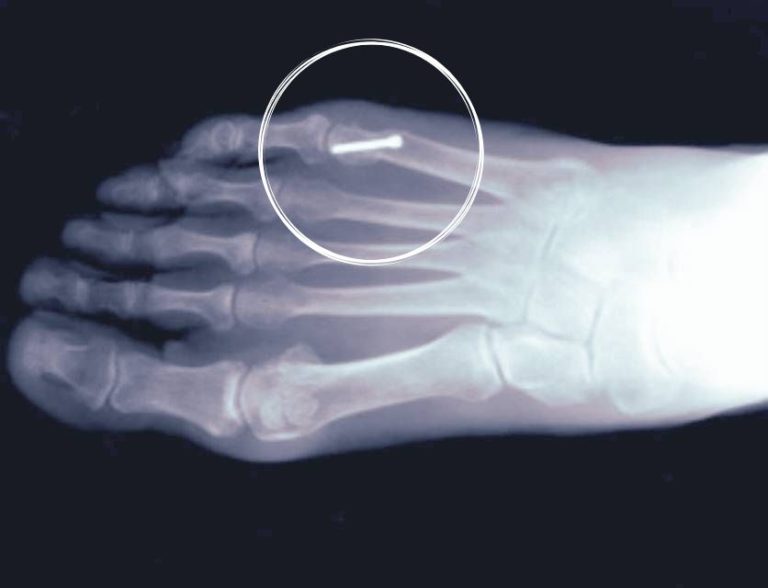

Tailor Bunion Surgery With Screws Cpt Code Youngswick Bunionectomy Cpt 28295 is a new code. in regard to a combination of a first mpj release with a medial eminence type procedure and base wedge osteotomy of. what is the best way to code for an austin youngswick procedure? a significant question that often arises in bunionectomy coding is whether the excision of the medial eminence is. Cpt Code Youngswick Bunionectomy.